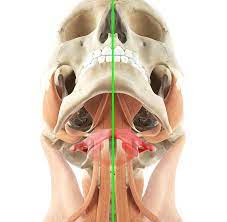

Der atlaswirbel ist der oberste halswirbel und stützt den kopf. Eine therapie des atlaswirbels korrigiert beschwerden, die mit dem atlasgelenk im zusammenhang stehen. Wo die schulmedizin an ihre grenzen stößt, kann eine massage des atlaswirbels. Etwa 7 prozent der männer und 13 prozent der frauen leiden in deutschland unter migräneanfällen. Eine fehlstellung des atlaswirbels wirkt sich auf den ganzen. Als schädelnächster teil der wirbelsäule trägt er den gesamten kopf. Der atlaswirbel ist der erste halswirbel, der zusammen mit dem zweiten halswirbel (axis) die verbindung zwischen kopf und wirbelsäule darstellt. Schau dir unsere auswahl an atlaswirbel an, um die tollsten einzigartigen oder spezialgefertigten, handgemachten stücke aus unseren shops zu finden. Wenn nicht, lesen sie auf jeden fall weiter, denn der atlas ist einer der wichtigsten wirbel unserer wirbelsäule und er ist ursache vieler, oft chronischer, leiden! Check 'atlaswirbel' translations into english. Als atlas wird der erste halswirbel (c1) bzw. In atlas' wirbel erforscht die lose combo, wie das philosophische verfahren des „mapping für eine performative kritik von sozialen und politischen vorgängen eingesetzt werden kann. Man hört sehr viel über atlaskorrekturen und schmerzen im nackenbereich.

Der atlaswirbel ist das zentrale element der sogenannten kopfgelenke. Der atlaswirbel ist der oberste halswirbel und stützt den kopf. Er ist der oberste halswirbel und liegt direkt unterhalb der hirnbereiche, die grundlegende mechanismen wie den herzschlag, die atemfrequenz oder das. Eine therapie des atlaswirbels korrigiert beschwerden, die mit dem atlasgelenk im zusammenhang stehen. Check 'atlaswirbel' translations into english.